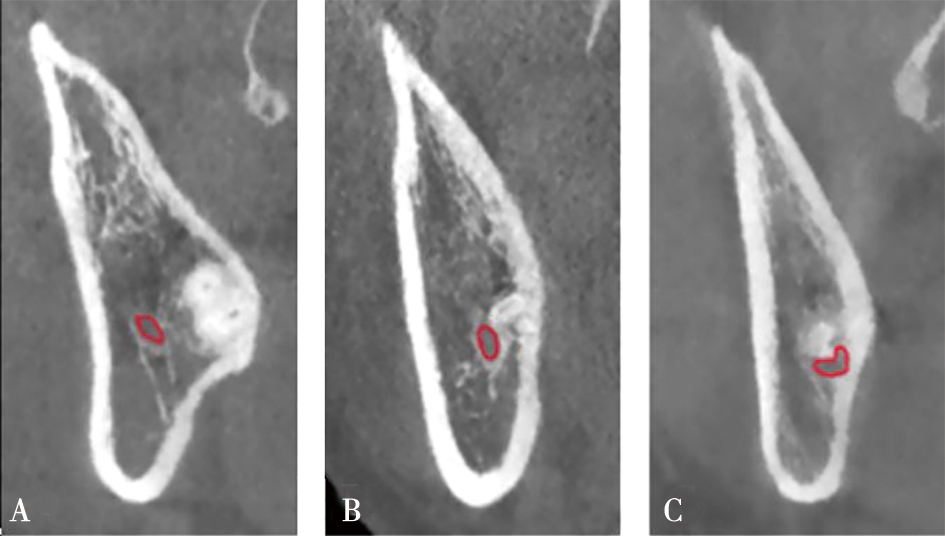

| 下颌管相对M3牙根的位置(CBCT) | 下方 | 816 | (70.77%) | 337 | (29.23%) | <0.000 1* | |

| 颊侧 | 1 173 | (67.92%) | 554 | (32.08%) | |||

| 舌侧 | 101 | (22.15%) | 355 | (77.85%) | |||

| 中间 | 6 | (11.32%) | 47 | (88.68%) | |||

| 下颌管形态(CBCT) | 圆形/卵圆形 | 2 014 | (88.02%) | 274 | (11.98%) | <0.0001* | |

| 狭窄型 | 82 | (7.45%) | 1 019 | (92.55%) | |||